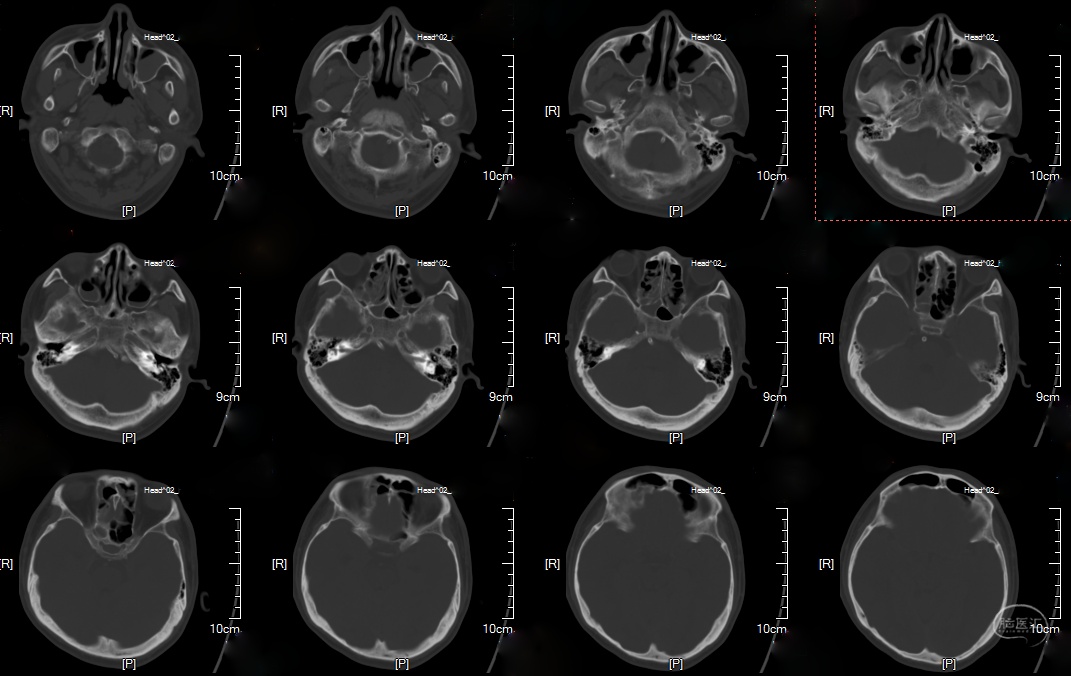

辅助检查:头颅CTA(外院)检查提示:椎基底动脉多发动脉瘤。

头颅CT及MRI: